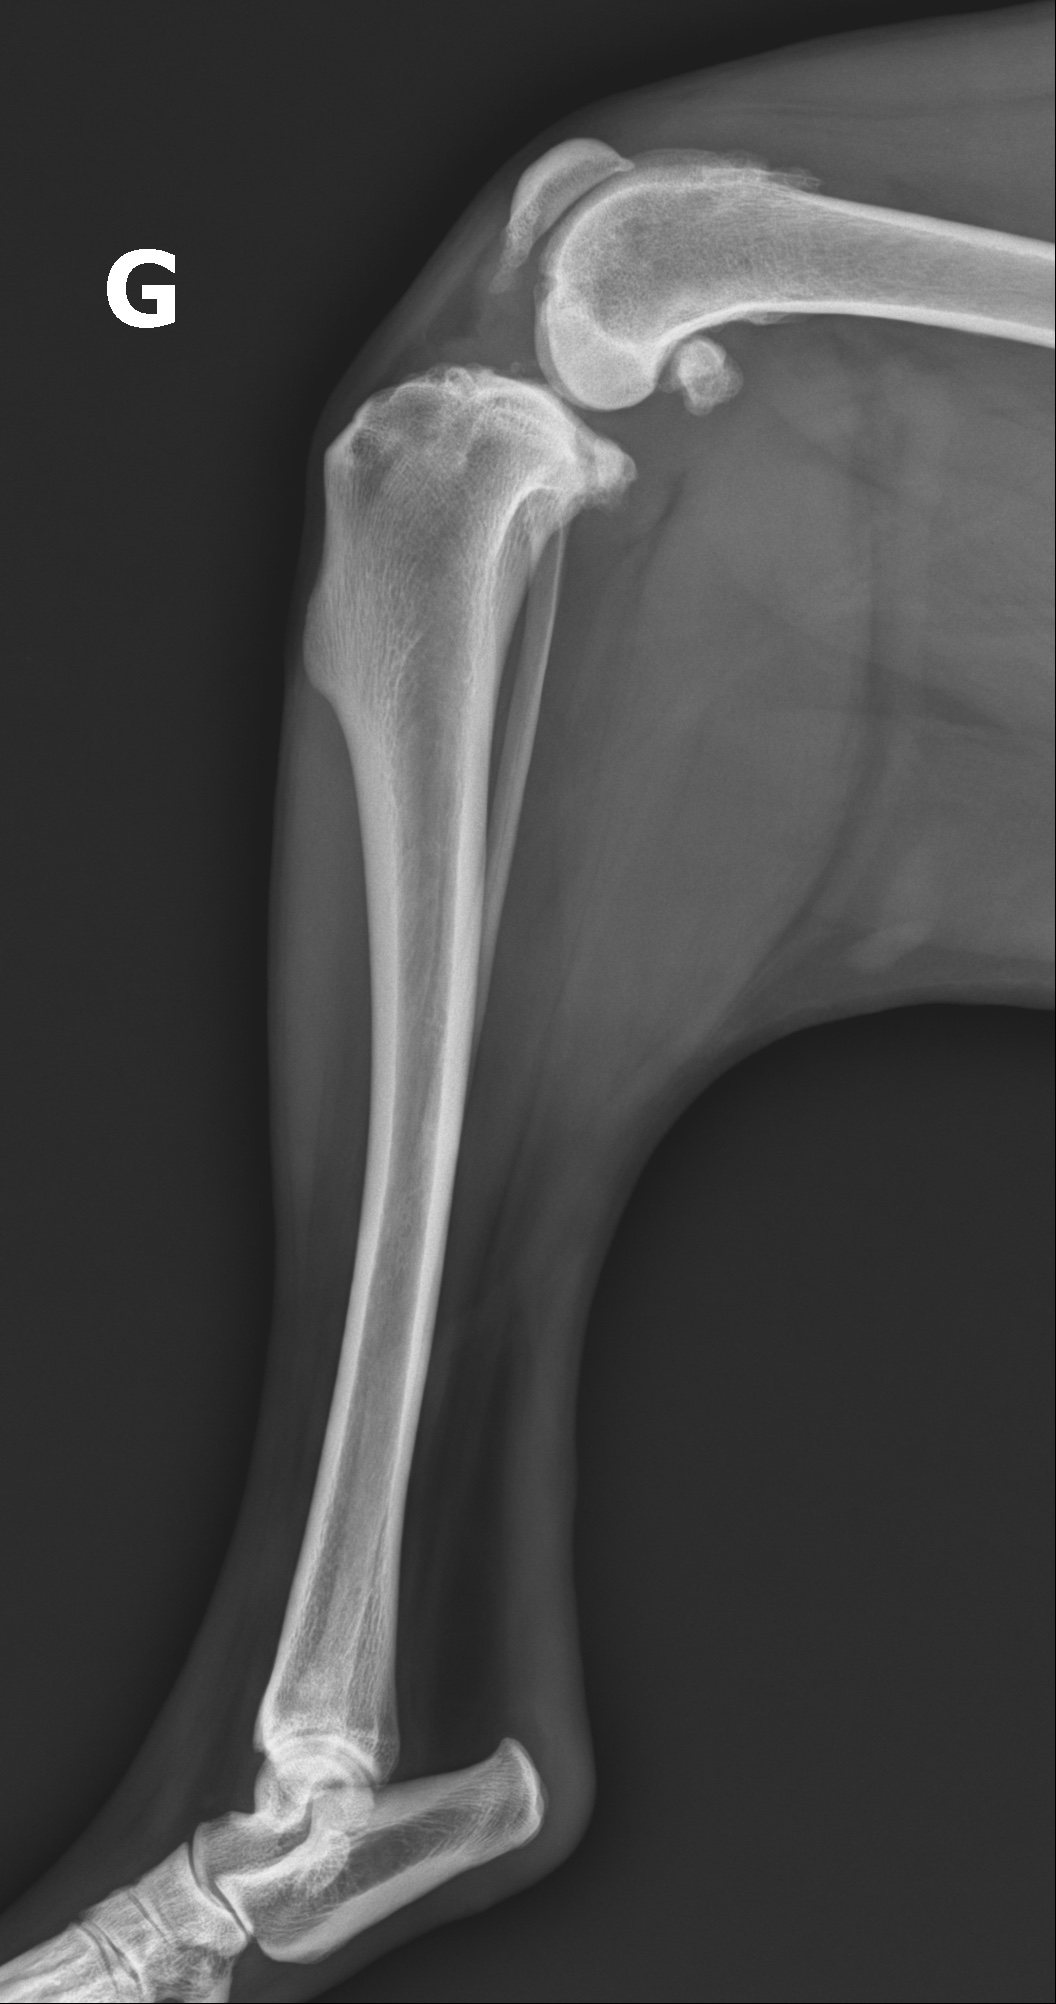

Vue radiographique préopératoire de profil du grasset gauche montrant une ostéophytose périarticulaire marquée